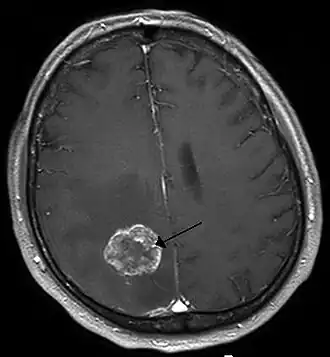

| Ressonância magnética de metástases de um cancro do pulmão no hemisfério cerebral direito . | |

Os tumores do cérebro secundários, ou metástases, são mais comuns que os tumores do cérebro primários.[2] Cerca de metade das metástases são provenientes do cancro do pulmão.[2] Os tumores cerebrais primários afetam por ano cerca de 250 000 pessoas em todo o mundo, o que corresponde a menos de 2% do total de casos de cancro.[3] Em jovens com idade inferior a 15 anos, os tumores do cérebro são a segunda principal causa de cancro, atrás apenas da leucemia linfoide aguda.[8]